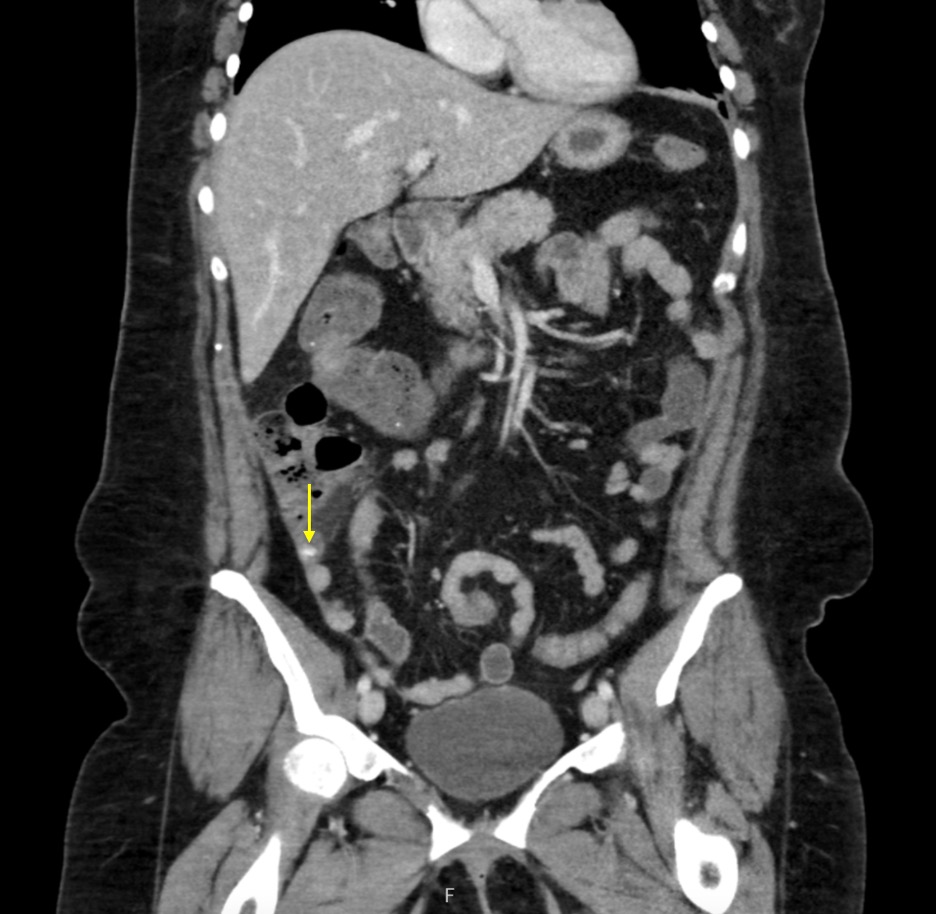

This case report highlights the clinical complexities of diagnosing and managing appendicitis complicated by appendicoliths in a 44-year-old female patient. Appendicitis is a common cause of acute abdominal pain, with imaging playing a crucial role in diagnosis. The patient presented with symptoms of right lower quadrant pain, nausea, vomiting, and chills that were initially misattributed to menstrual cramps. Diagnostic evaluation revealed multiple appendicoliths via computed tomography (CT), and the decision for laparoscopic appendectomy was based on the imaging results and clinical presentation. Intraoperative findings showed gangrenous but non-perforated appendicitis. The patient’s postoperative recovery was uneventful, with successful symptom resolution. This case highlights the importance of considering appendicitis in the differential diagnoses for acute abdominal pain in females, particularly with overlapping gynecological symptoms. The high sensitivity of CT imaging for appendicitis and the necessity of timely surgical intervention in cases involving appendicoliths are discussed. Multimodal imaging and prompt surgical management are vital for favorable outcomes in complicated appendicitis cases.